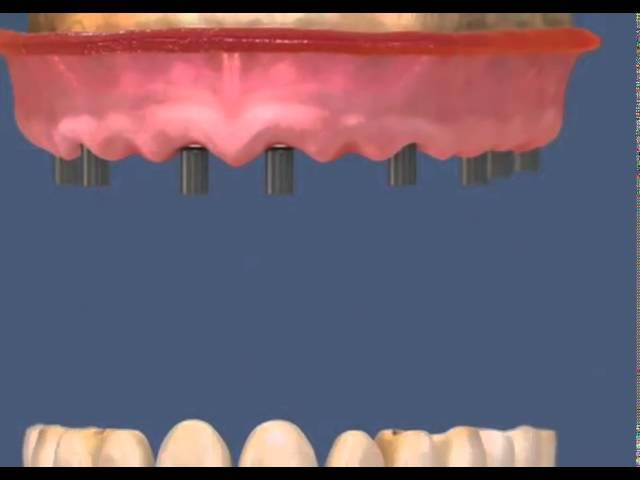

несъемная конструкция на 8 имплантах на верхн. челюсти